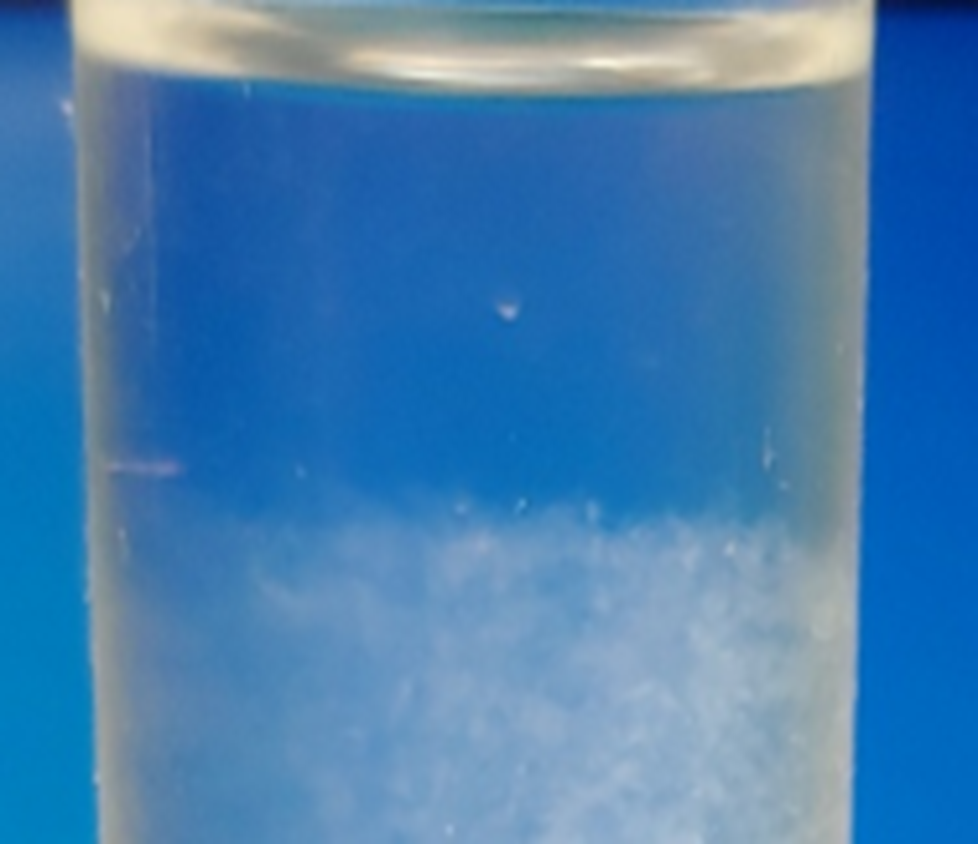

EBIR-20D :

PEO 기반

Gel-beads